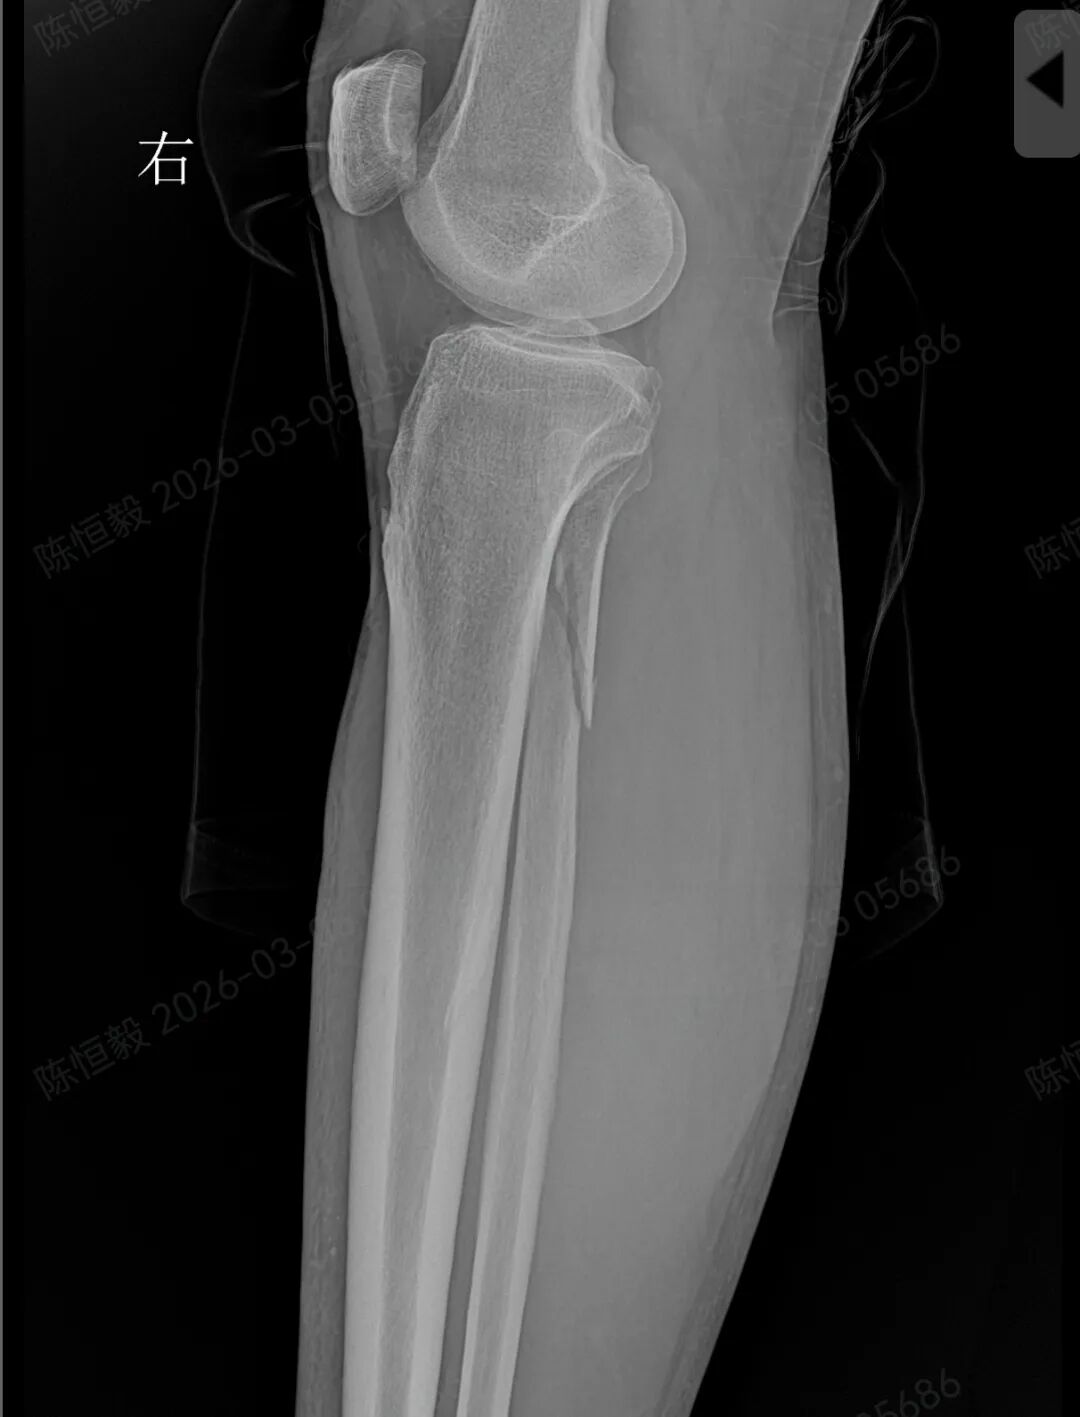

王大爷听从建议住院后,经完善体格检查及 CT 检查,最终确诊为复杂的 Maisonneuve 骨折:不仅存在下胫腓分离,还合并前踝 Chapute 结节撕脱骨折、后踝骨折、内踝骨折,同时伴有腓骨高位骨折。